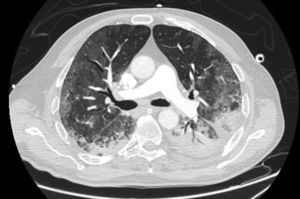

LDH has a significant positive correlation with the severity of pneumonia quantified on initial computed tomography (CT) in COVID-19 patients.11 Patients with severe disease presented higher levels at admission than those with a non-severe disease.12 Hence, LDH indicates the severity of tissue damage and the risk of worsening. The most characteristic chest CT abnormalities in COVID19 pneumonia were pure ground-glass opacities (GGO) (Supp. Figure 2) or mixed with consolidation (supp. Figures 3-4) or a reticular pattern, usually multifocal, asymmetric, bilateral, and peripheral, most commonly located in the inferior lobes.13 GGO is a radiological term revealing an area of increased, hazy lung opacity through which bronchial structures and vessels are still visible, consolidation was defined as the presence on a chest CT of opacities with obscuration of the pulmonary vessels’ airway walls.

Pneumomediastinum (PM) is a condition where the air is present in the mediastinum. Free air leaks from ruptured alveoli, dissecting along the bronchovascular sheaths towards the mediastinum. PM, as seen on chest CT, elevates the mediastinal pleura and can extend into the neck or chest wall.14 One of the first signs that simulate a pneumomediastinum is the Mach band effect. This optical effect at the margin between areas of faintly different density15 can mimic various other pathologies (pneumopericardium, fracture), and makes it possible to suspect PM in COVID-19 patients. Non-traumatic PM is a rare complication of COVID-19 pneumonia.16 Its development in COVID-19 infection is also considered a possible indicator of disease worsening, which may be or not be associated with invasive ventilatory support. Spontaneous PM seemed to be a frequent complication of severe acute respiratory syndrome (SARS).17 In 2004, a high peak LDH level of 863 IU/L had been correlated with spontaneous PM in SARS patients, likely due to significant remodeling of the lung tissue causing leakage and vessel wall dissection.17 Most patients with PM had lung involvement higher than 50% at the moment of the diagnosis,18 corroborating the increased risk of rupture and PM development. This study aimed to evaluate the association between baseline serum LDH levels and COVID19 lung necrosis outcome based on the extent of lobar involvement and PM development.

In our study, CT was used to identify and confirm spontaneous PM and PM relative to mechanical ventilation. The scannographic signs of PM relied on the anatomical region occupied by the air as it exits the mediastinum.20 (Figs 1, 2).